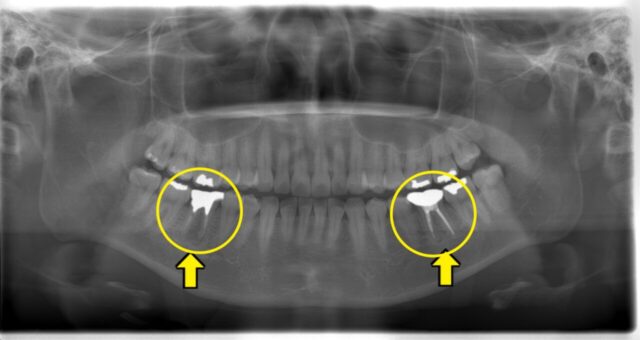

神経を抜かないといけなくなった歯が2本あります。なぜでしょうか?

その答えは「オープンバイト」という奥歯だけが当たって前歯が当たっていない噛み合わせが原因でした。

❓なぜトラブルを起こすのか❓

正しい噛み合わせは、前歯も奥歯も全体がバランスよく噛み合うものですが

奥歯だけが当たっている噛み合わせの為

奥歯の負担が大きくなってしまい、詰め物や被せが欠けたり外れたりを繰り返すなど

最悪の場合、根が割れて抜歯になってしまうケースも…